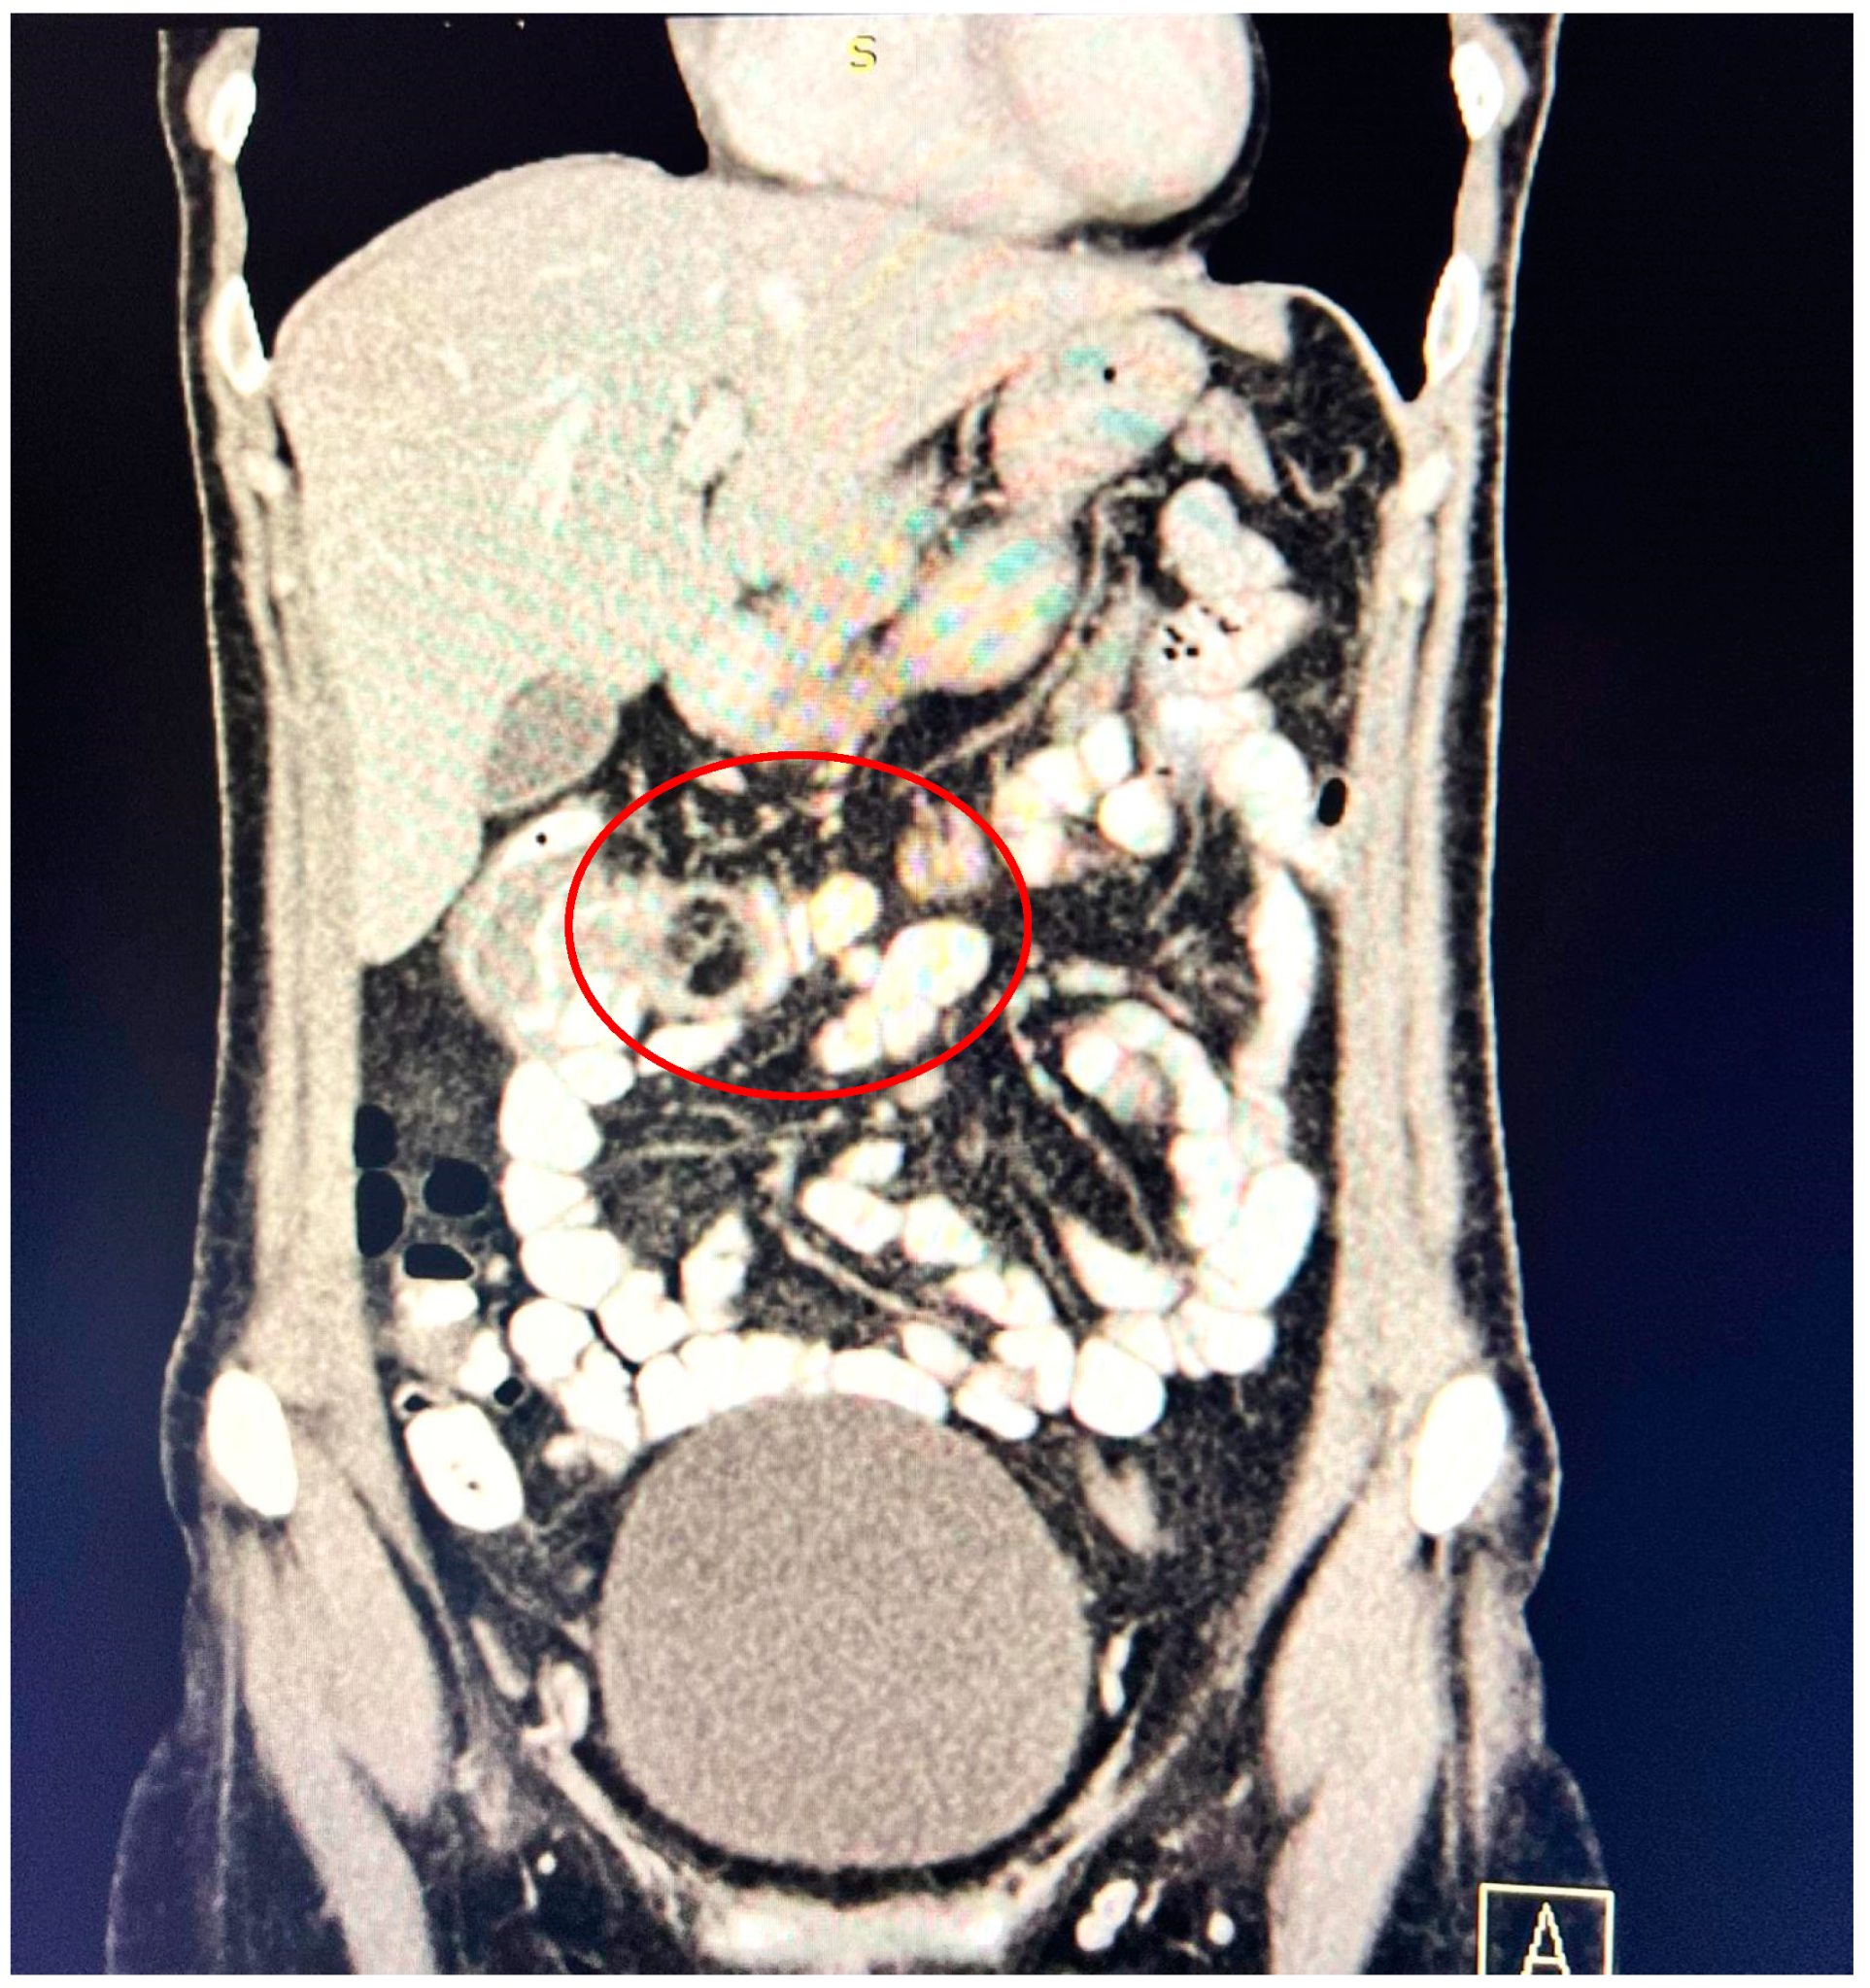

A contrast-enhanced computed tomography (CT) scan conducted on the day of admission revealed circumferential parietal thickening of a maximum of 21 mm at the hepatic flexure of the colon. This thickening extended over a length of approximately 45 mm, resulting in filiform, axial stenosis of the lumen, without any overlying distension of the colonic frame. The parietal thickening was moderately iodophilic and accompanied by discrete linear-type densification of locoregional fat, which was most likely a desmoplastic reaction. A tumor formation with a maximum axial diameter of approximately 29/28 mm, extending craniocaudal on a length of approximately 27 mm, was located at the distal end of the parietal ingrowth with an intraluminal site. This tumor formation had a polycyclic contour, thin septa within, and a discrete lodophilic peripheral appearance. It appeared to have a wide base of implantation at the level of the postero-inferior wall of the colon; mild hepatomegaly in the liver, with a homogeneous structure and a regular surface, and the absence of focal primary or secondary lesions; adenopathies in the hepatic hilum with a maximum diameter of 16/12.5 mm and in the celio-mezenteric territory with a maximum diameter of 24/19 mm; microadenopathies with the gastro-hepatic ligament; and an absence of subdiaphragmatic fluid (Figure 1, Figure 2 and Figure 3).

Figure 1.

Circumferential parietal thickening noted at the hepatic flexure of the colon measuring 21/45 mm, moderately iodophilic, associated with discrete linear-type densification of locoregional fat, indicative of a desmoplastic reaction.